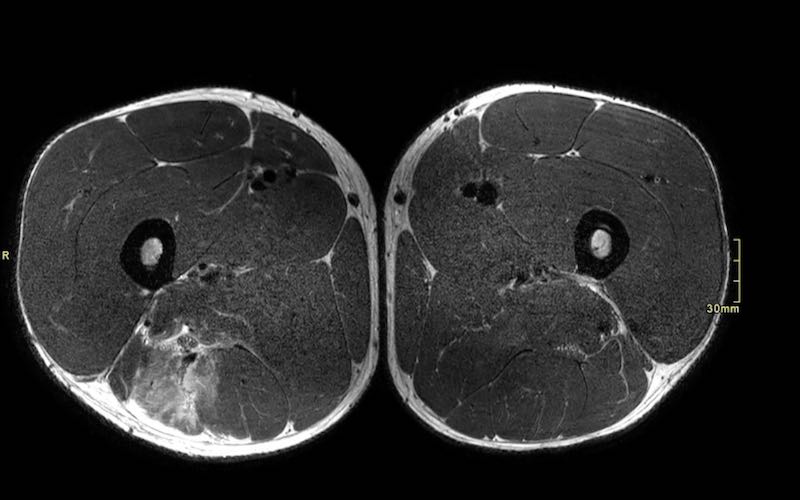

Trên các hình ảnh axial này, có thể thấy tăng tín hiệu và dày lên của gân cơ nhị đầu đùi bên trái (vòng tròn chấm vàng) khi so sánh với bên không bị tổn thương (vòng tròn chấm trắng).

Tại đây bạn có thể cuộn qua các hình ảnh axial. Có thể phóng to hình ảnh bằng cách nhấp vào chúng.

Đây là tổn thương bán phần, bắt đầu từ gân chung ở phía gần, bao gồm cả vùng MTJ và gân trong cơ ở phía xa hơn. Chiều dài vùng phù nề và mức độ biến dạng gân đều ở mức độ cao. Trường hợp này được phân loại là tổn thương BAMIC 3b/c.